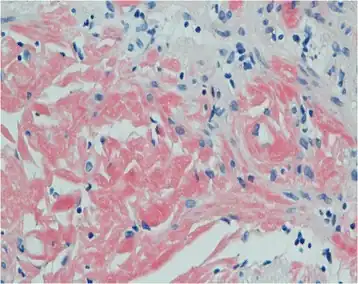

| Primary systemic amyloidosis initially presenting with digestive symptoms-gastric mucosa showed orange-red positivity | |

Both blood and the urine can be tested for the light chains, which may form amyloid deposits, causing disease. However, the diagnosis requires a sample of an affected organ.[5][8] Other diagnosis can be tissue biopsy. Tissue biopsy tests a tissue sample to look for amyloid deposits. The tissue is stained with red dye, and under a microscopic examination, amyloid proteins can be detected if the tissue turns an apple-green color. [9]